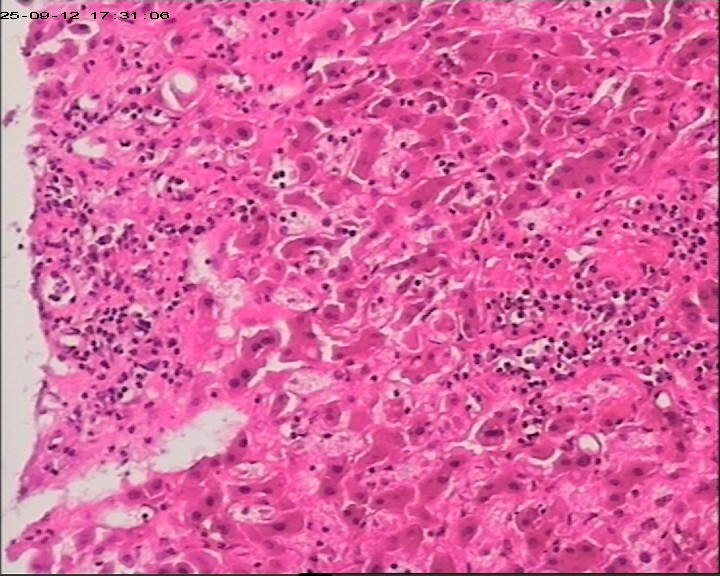

性别年龄47岁临床诊断肝占位性质待查,肝棘球蚴病?

标本名称肝组织

大体所见肝组织一块,大小为20*18*15cm,切面多房囊性,部分内含坏死样物。

建议:描述性病理诊断!(感觉符合棘球蚴病病理改变,但未见明显的直接证据!)

大体检查有没有看到粉皮样的角质膜?取角质膜在镜下找到头节有助于诊断。